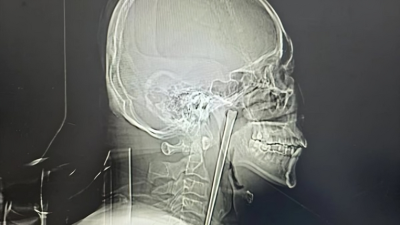

وأظهرت الأشعة وجود جسم معدني بطول 12 سنتيمترًا عالق داخل حلق المريض، وعند سؤاله، أوضح أنه ابتلع هذا العود عن طريق الخطأ قبل نحو 8 سنوات أثناء تناول الطعام، دون أن يتخذ أي إجراء طبي جاد في ذلك الوقت.

وقرر الفريق الطبي إجراء جراحة دقيقة طفيفة التوغل عبر الفم، لتجنب شق الرقبة، وتمكنوا بالفعل من استخراج العود المعدني بالكامل دون مضاعفات تُذكر.